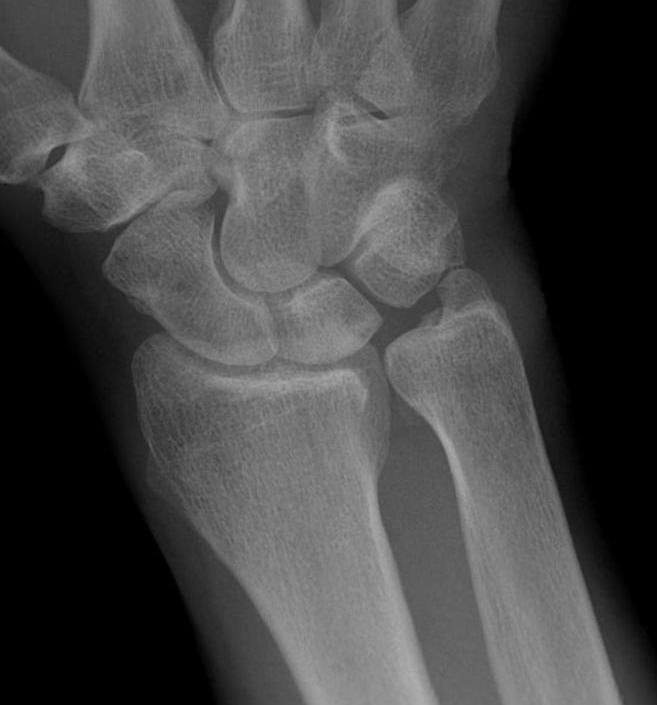

Xrays

Ulna variance

Wide variation in the population - increased load on TFCC with ulna positive

Xray in neutral supination / pronation

- variance is not static and varies up to 3 mm with wrist position

- ronation increases ulnar variance

- supination decreases variance

Transverse line of lunate fossa to transverse line of ulna head

Ulna neutral

Ulnar negative

Ulna positive